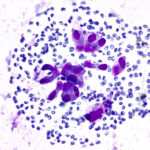

Slide Quality

Our propriety monolayer preparation ensures minimal cellular overlap, giving a clear view of cellular features. Every slide looks expertly done—even without the expertise.